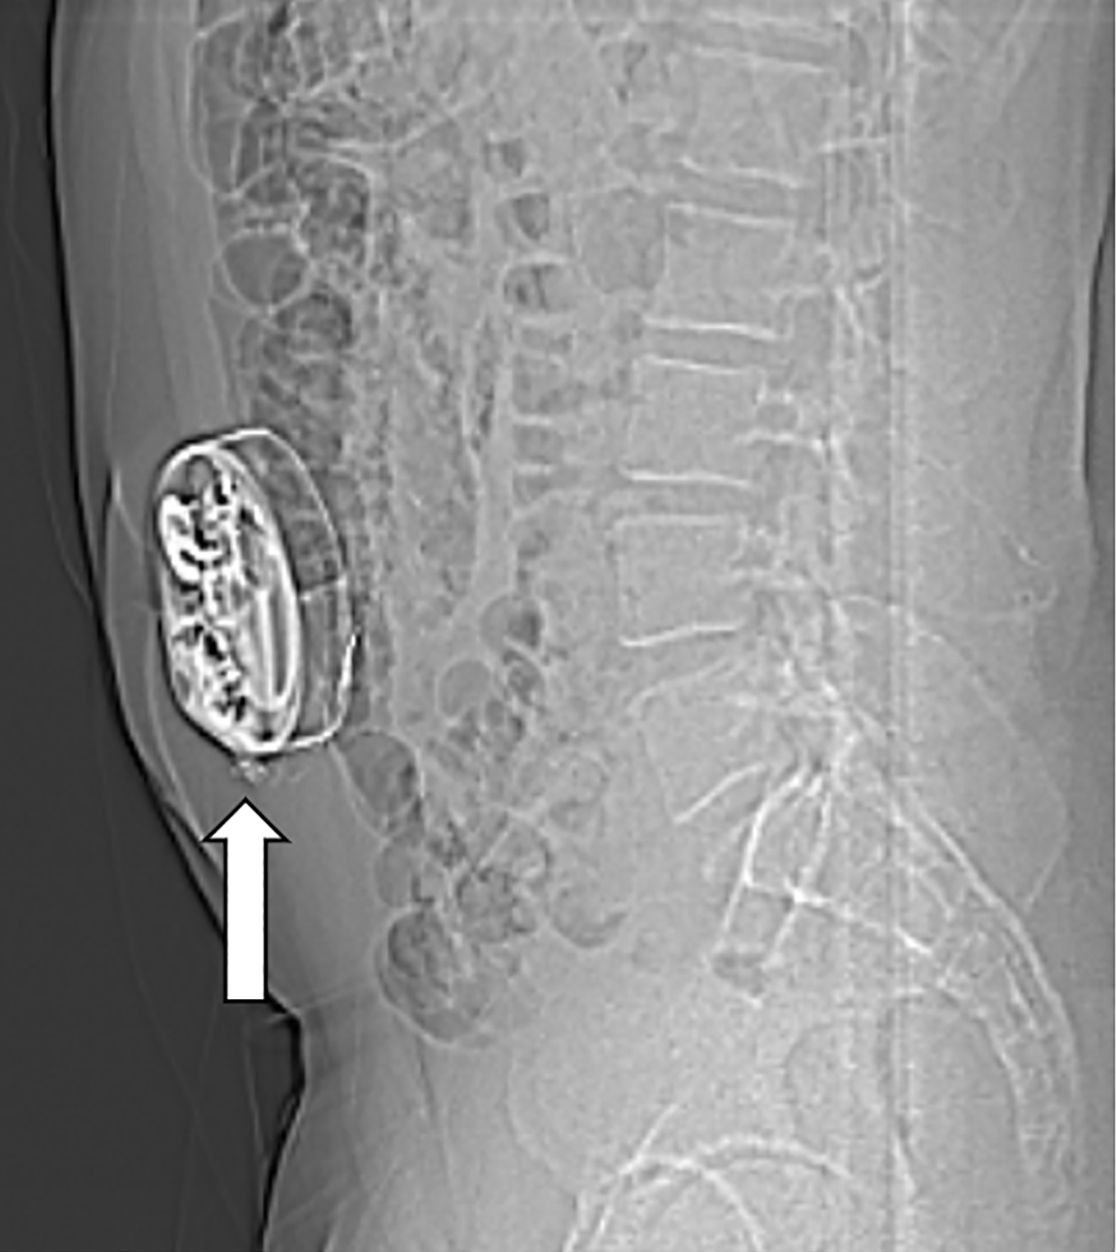

Im Nervenwasserraum (Liquor) einliegender Schlauch zur intrathekalen Therapie (Pfeil)

Am Bauch implantierte Medikamentenpumpe (Pfeil)